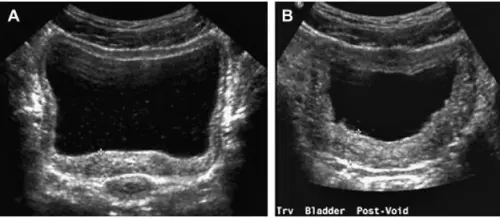

Додаткові вимірювання. Після первинного огляду пацієнта просять спорожнити міхур для оцінки залишкової сечі.

оцінку залишкової сечі

залишкова сеча: не більше 50 мл